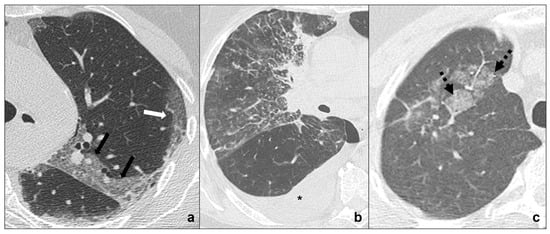

- Early phase or phase one (between day 0 and day 4) is characterized by bilateral and diffuse subpleural ground-glass opacities (Figure 1a);

- Progressive phase or phase two (between day 5 and 8) shows extensive subpleural crazy paving areas co-existing with ground-glass opacities. Small consolidative foci may be present (Figure 1b);

- Peak phase or phase three (between day 9 and 13) is defined by subpleural consolidation with peripheral ground glass and/or crazy paving opacities (halo sign) (Figure 1c);